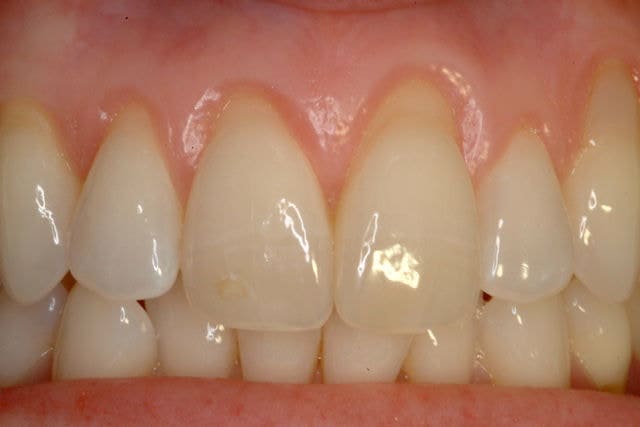

After